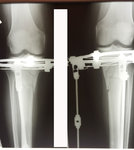

рентген в 55 дней с момента операции.

Сращение идёт отлично, снятие аппаратов планируется через 3 недели.